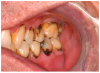

Mucosal lesions are characterized by three main signs: 1) lichenoid inflammation, 2) erythema, and 3) ulcerations.20 Lichenoid inflammation appears as white reticular streaks or lacey lines that resemble Wickham striae observed in oral lichen planus and are considered to be a diagnostic feature of oral cGVHD7,30 (Figure 1a). While these lesions may occur anywhere in the oral cavity, they most frequently appear on the buccal mucosa and tongue.31,32 Lichenoid lesions may be accompanied by varying degrees of erythema and ulceration, which are features often associated with more severe symptoms (Figure 1b-c). Ulcerations represent a breakdown in oral mucosa and can be particularly symptomatic, limiting functions such as oral nutrition, speech, and oral hygiene maintenance.33

Figure 1b. Lichenoid erythema

Figure 1b

Figure 1c. Lichenoid ulceration and erythema

Figure 1c